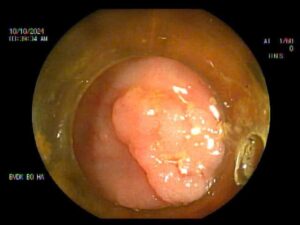

Vừa qua, Bệnh viện Đa khoa Bố Hạ ghi nhận nhiều trường hợp bệnh nhân đi khám sức khỏe định kỳ, quá trình nội soi đại tràng phát hiện nhiều polyp với kích thước lớn.

Polyp đại tràng là một dạng tổn thương niêm mạc đại tràng và tổ chức dưới niêm mạc tăng sinh hình thành lên với đặc điểm:

– Có cuống hoặc không có cuống

Các khối Polyp này có thể lành tính hoặc ác tính phụ thuộc vào kích thước và vị trí của polyp trong đại tràng:

– Polyp tăng sản: không có nguy cơ biến chứng thành ung thư

– Polyp u tuyến: tiền thân của hầu hết bệnh ung thư đại tràng

Trong trường hợp để lâu, polyp lớn, nguy cơ ung thư hoặc tiền ung thư đại tràng là rất cao.

Nội soi đại tràng là một trong những biện pháp hiệu quả nhất để phát hiện chính xác polyp đại tràng.